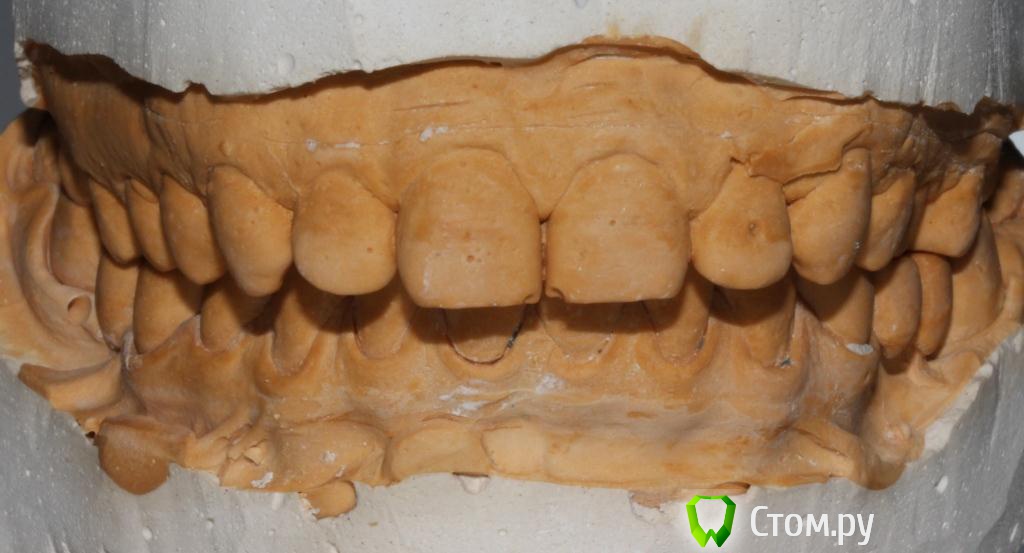

zzkz Опубликовано 6 марта, 2014 Поделиться Опубликовано 6 марта, 2014 Пациент 32 лет от роду. Известная особа в шоу бизнесе.С полостью рта не айс.Помогите разобраться и составить план лечения. Без лица(фото не делал) Жалобы на дискомфорт, трудность пережевывания пищи, с ее слов - как будто левая сторона не достает, в общем испытывает не удобства одни. На эстетику как ни странно ноль внимания. ВНЧС слева легкий щелчок при открывании/закрывании. Мышцы в норме. Но в фас и профиль подбородочная складка довольна выражена, как характерно при 2-ом классе. Фото моделей и панорама прилагаю Мой план пока таков:1. удаление 2-х восьмерок на н\ч2. каппа прозрачная, чтобы проверить реакцию ВНЧС при поднятии прикуса на пару месяцев3. снятие коронок4. воск5. импланты с аугментацией6. временное на металлопластмассе на имеющихся зубах7. через 4-5 мес. постоянные на имплантах как бы сделали Вы? Ссылка на комментарий

Bobby Опубликовано 7 марта, 2014 Поделиться Опубликовано 7 марта, 2014 (изменено) Сначала узнайте готова ли она проходить лечение не менее двух лет, не нарушая при этом график лечения? Мой скромный опыт подсказывает, что личение публичных людей не столь сложно с медицинской точки зрения, сколь с организационный (частые отмены визитов, капризы, не своевременная оплата оказанных услуг). Касаемо клинической ситуации. В идеале провести ортодонтическое лечение, чтобы изменить овербайт и оверджет. Увеличение вертикального расстояния окклюзии (высоты прикуса) у пациентов со 2-м классом (дистальный прикус) всегда переносится хуже и в случае не создания на керамике ретрузионной защиты, может приводить к дискомфорту и даже дисфункциям жевательного органа. Реставративное лечение требуется только в боковых участках? Каково состояние передних зубов?Нужно ТРГ. Изменено 7 марта, 2014 пользователем Bobby Ссылка на комментарий

zzkz Опубликовано 7 марта, 2014 Автор Поделиться Опубликовано 7 марта, 2014 сделайте ТРГ, самому станет понятнее)если бы я читать мог ТРГ(ну да ладно. От ортодонтии отказ, певица, боится нарушений с дикцией и т.п. частые отмены визитов, капризы, не своевременная оплата оказанных услуг в точку! пару посещений пропустила уже у меня и терапевта)) И поведение как будто мы ей должны и обязаны чем то Реставративное лечение требуется только в боковых участках? Каково состояние передних зубов? фронт композитные реставрации, (мне нравится, ее устраивает-по ТВ не видно), думаю там будет Emax в будущем, хотя она об этом пока не знает)) Я предложу во всяком случае. Сделаю фото она сама все увидит. Настаивать на ортодонтии? Ссылка на комментарий